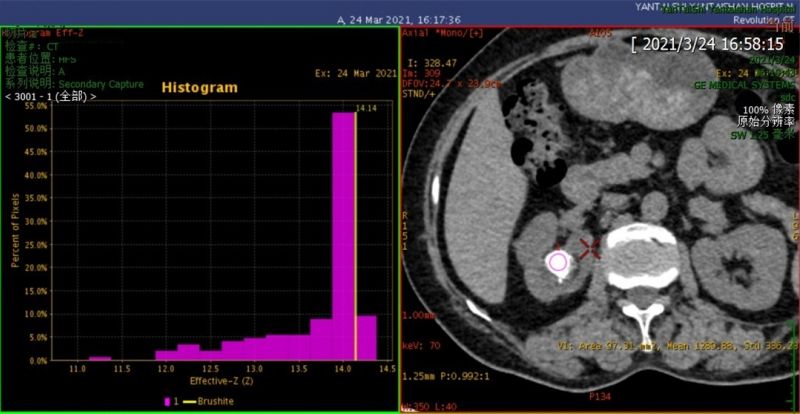

能谱CT泌尿系统结石分析检查显示,患者右肾结石为混合性结石,感兴趣区内以磷酸氢钙为主,占比53%,其次是草酸钙,占比20%。

烟台山医院的GE超高端256排Revolution CT是目前我市唯一的一台超高端能谱CT。它不仅拥有宽体能谱成像技术,而且具有高度智能化的后处理流程。通过将混合能量图像拆分成单能量图像进行分析,可明显提高阴性结石的检测率,并实现物质分离定性,形成有效原子序数直方图,使结石成分一目了然。